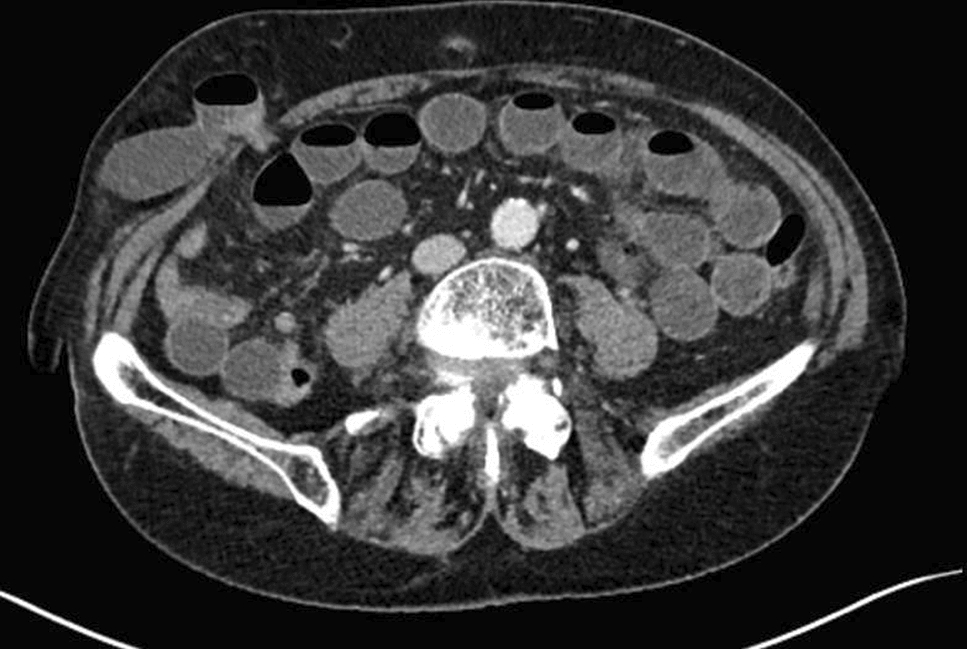

• Figs. 4,5: CT—scan of selected spigelian hernias

Fig. 5

CT-Scan of right spigelian Hernia (Foto

© U. Volmer)